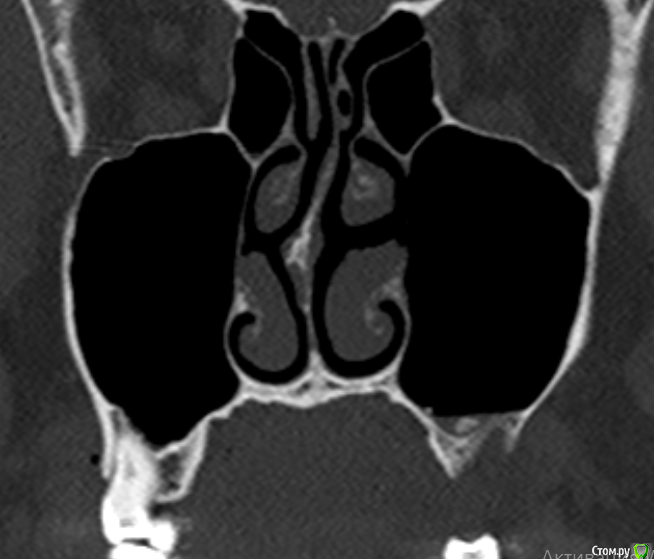

Фрагмент кости в гайморовой пазухе. Нет гноя. Причина болей?

Здравствуйте. На протяжении 5 месяцев беспокоит боль в области между левой пазухой и челюстью. Боль острая, ноющая как при боли в зубе. Верхняя 7а слева (депульпированная) удалена месяц назад, но боль только усилилась. Со временем стали болеть и все суставы в теле, в особенности руки и ноги. Выполнять простые движение стало очень больно. На КТ видны инородные фрагменты и нарушение целостности нижней стенки пазухи, но в Спб никто их не захотел удалять инородные фрагменты из-за того, что причина боли по мнению врачей не в этом. В результате боль только усиливается. Причину боли при моей картине КТ никто установить не может. Обращалась почти во все клиники. Несколько неврологов патологию лицевого нерва исключили. Все это время держится температура 37-37,5. Ощущение сильного воспалительного процесса, боль немного стихает на приеме антибиотиков, но ненадолго, примерно на неделю - две. Обычные обезболивающие совершенно не помогают. Жевать пищу очень больно, сильно рот не открыть. Слабость и нет аппетита. Может ли так организм реагировать на инородный фрагмент кости в пазухе или дело в другом? Возможно ли что есть какие-то нарушения (переломы, трещины и пр) кости, которые требуют хирургического вмешательства?Вопрос возник по той причине, что при промывании пазухи есть ощущение проникания жидкости куда-то за пределы слизистой и после промывания состояние заметно ухудшается. Если кто-то может помочь советом буду очень признательна. Есть несколько КТ 3д. https://yadi.sk/d/PX30GoO1Cn5m_w -  от 13.06.2020 (примерно сразу после появления болевого синдрома), https://yadi.sk/d/bm7FD9SYVw2-Gw- сразу перед удалением зуба,  https://yadi.sk/d/fbaOTQT2-ya4xQ - КТ пазух от 21.11.2020 (то что есть на сегодня).